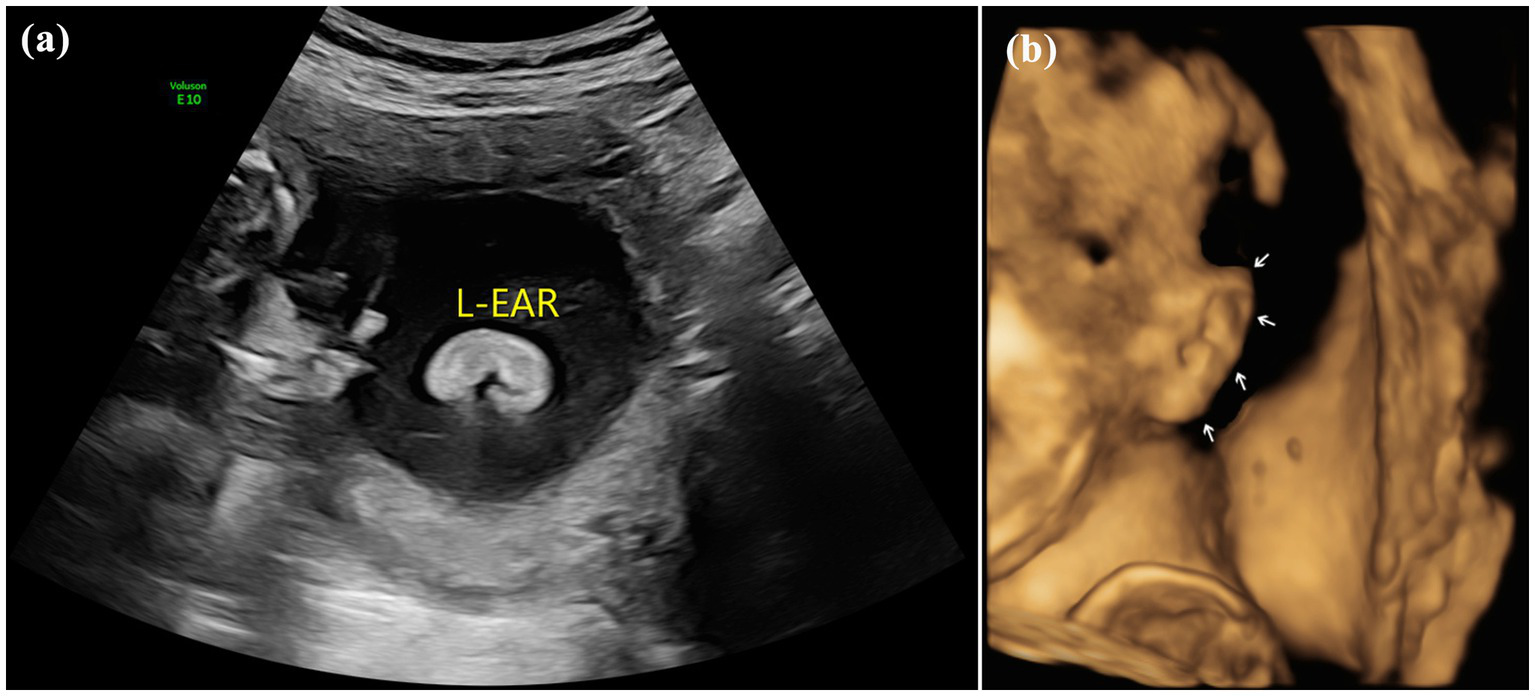

Figure 2

Images of type II of microtia: (A) 2D sonography of microtia; (B) 2D sonography of contralateral ear(normal); (C) 2D sonography of unilateral microtia type II with normal external acoustic meatus; and (D) 3D sonography of Unilateral microtia type II.